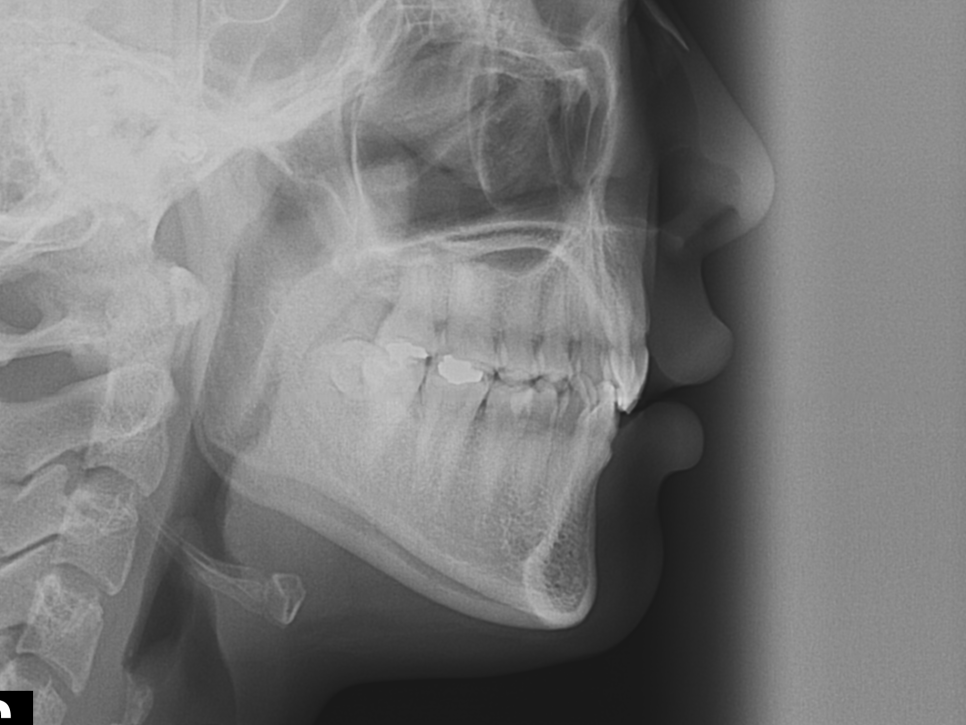

환자분의 치아를 진단한 결과

/90도 회전 측절치 개선

/전치부 배열을 위한 앞니교정

[교정 예상 기간 6개월 전/후]